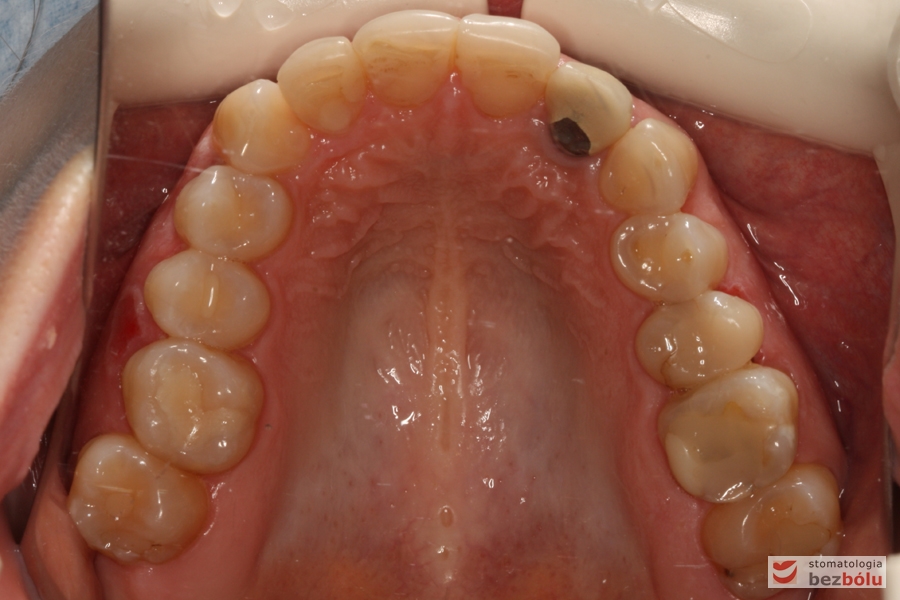

Szczęka - widok okluzyjny, nieregularny kształt łuku zębowego, metal na dwójce górnej

Szczęka – widok okluzyjny, nieregularny kształt łuku zębowego, metal na dwójce górnej